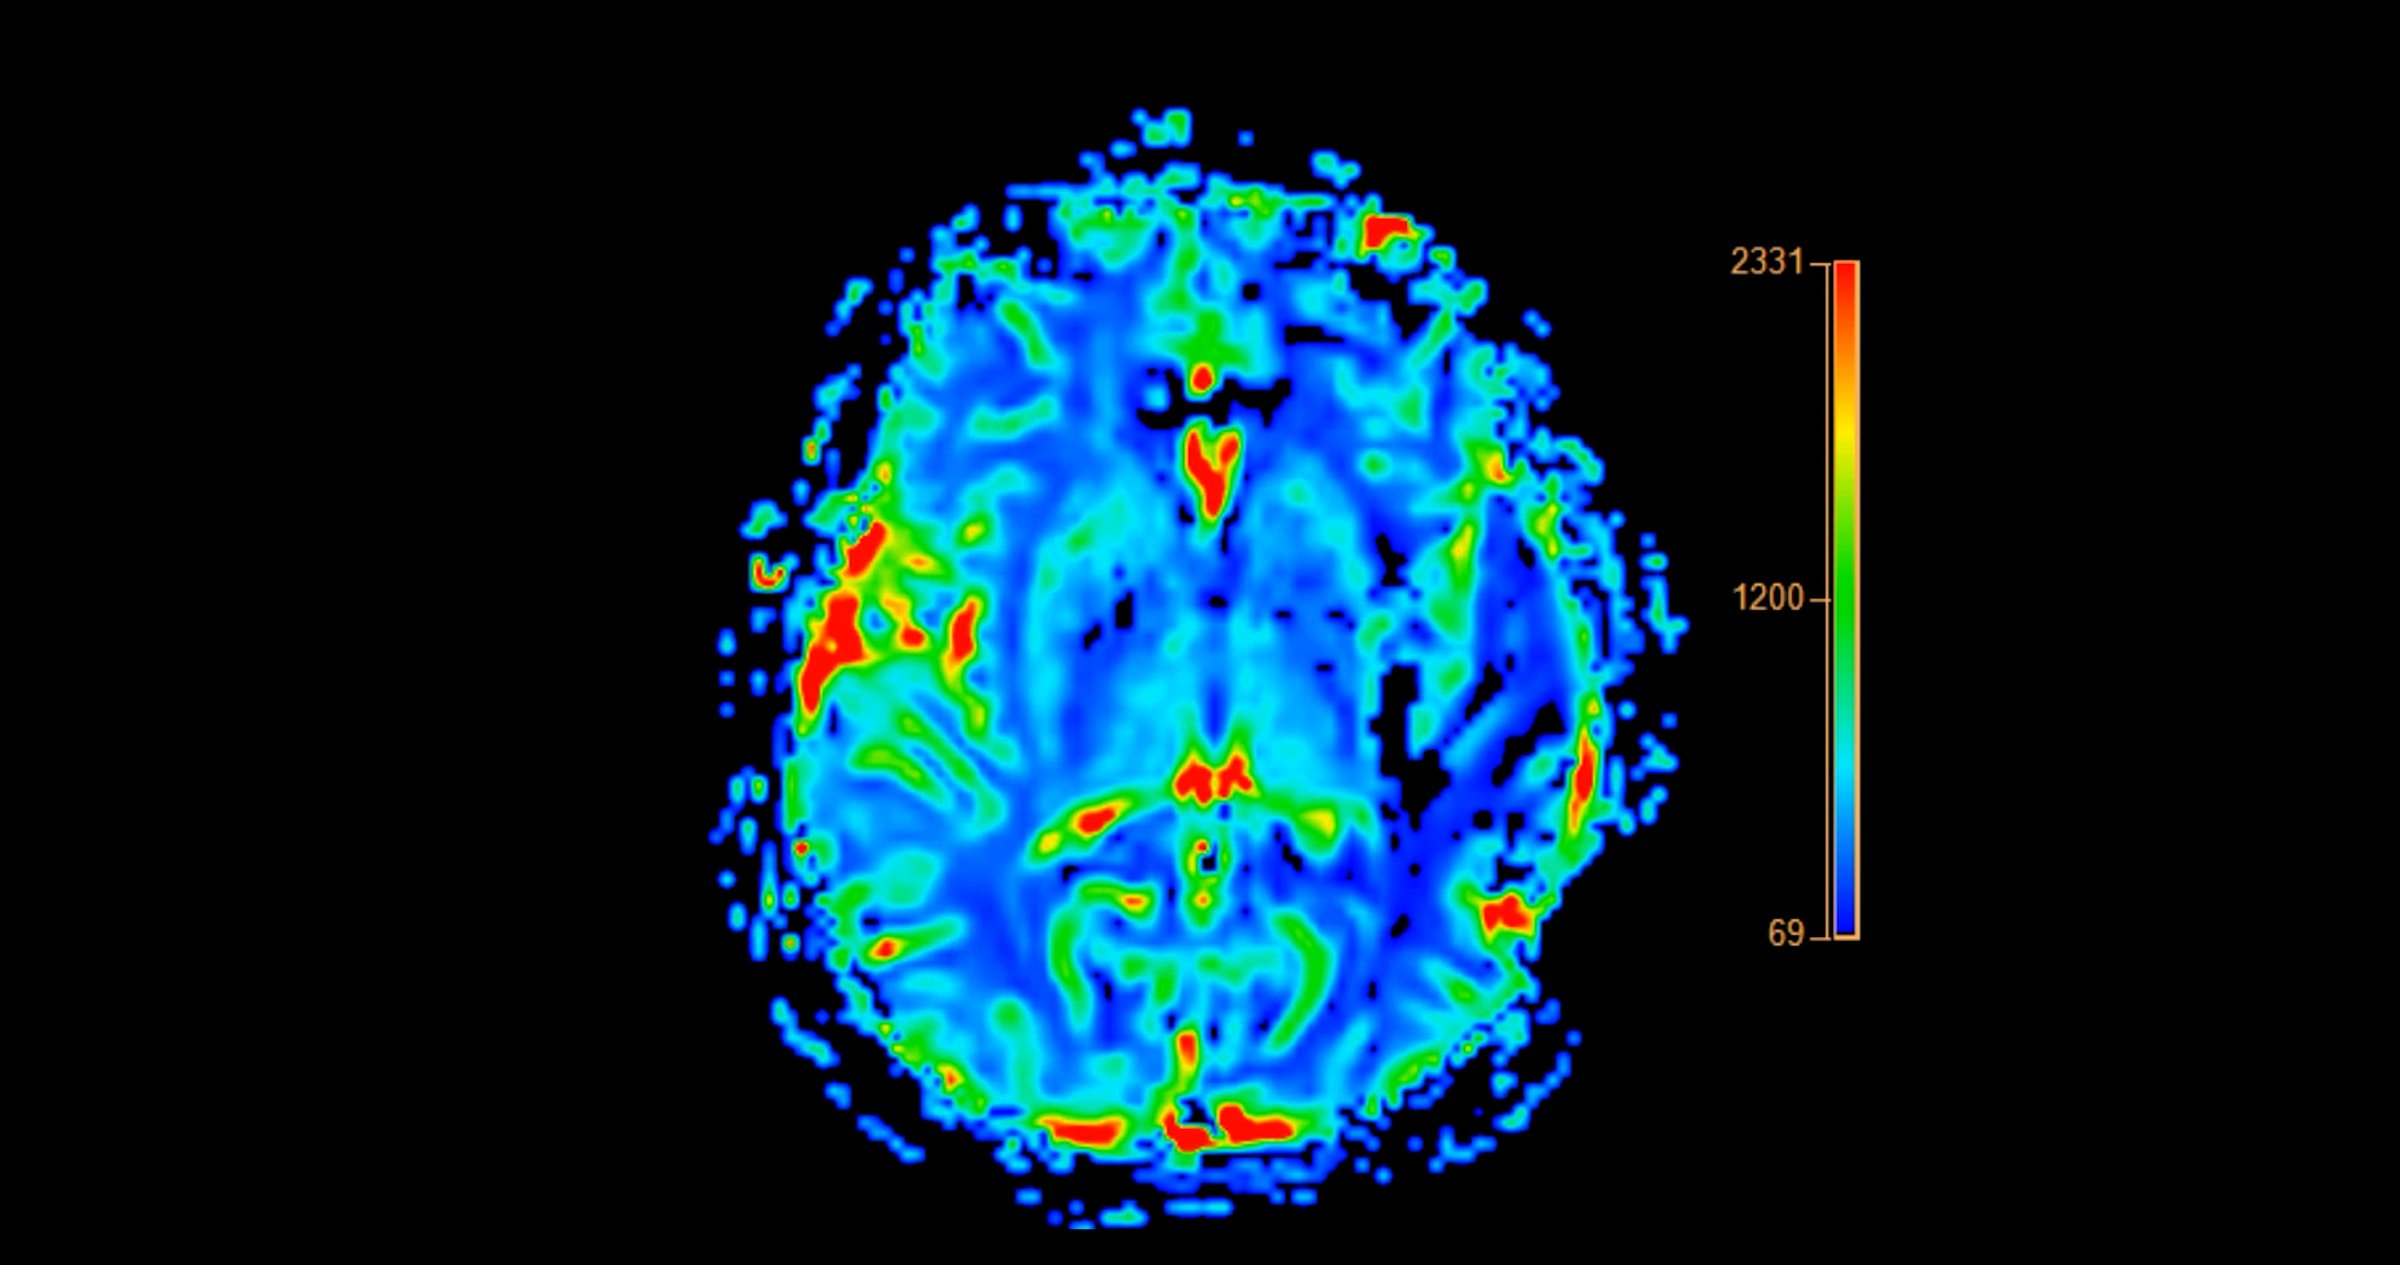

MRI brain perfusion imaging helps assess cerebral blood flow and tissue viability. It aids in diagnosing strokes, tumors, and other neurological conditions.